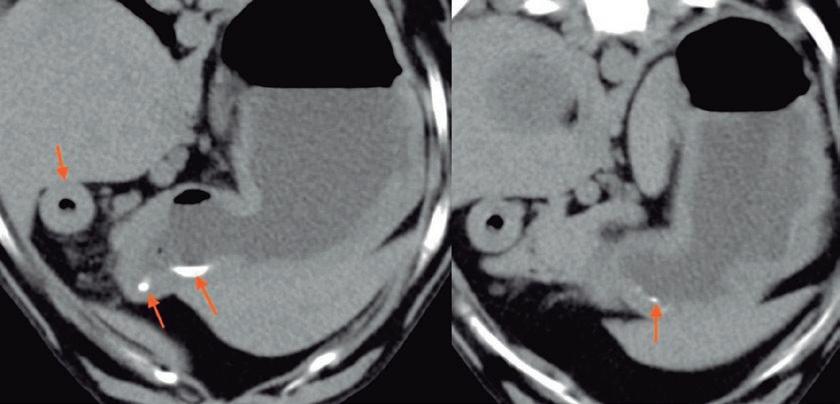

Argos 247 by Grupo Asís - Issuu